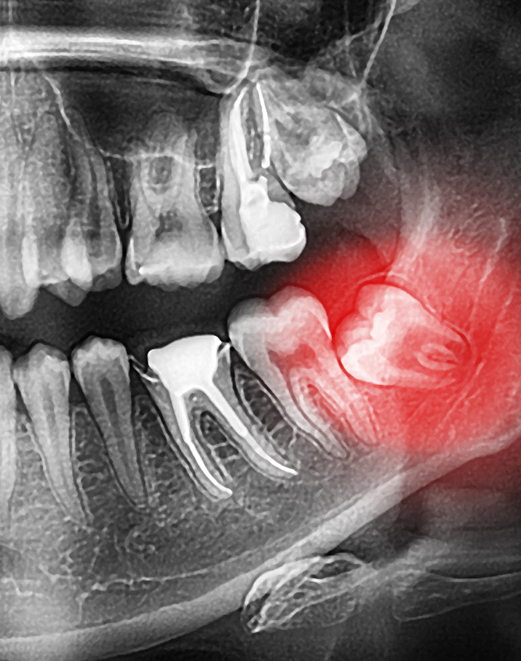

C’est donc pour éviter ces différents problèmes causés par les dents de sagesse qu’on les retire. Cette procédure plus ou moins complexe — selon la forme et la position de la dent et de ses racines — peut être réalisée de façon totalement préventive, avant que les troubles apparaissent ou pour enrayer une infection. Dans tous les cas, elle est finement planifiée et réalisée en se basant sur une évaluation complète incluant des radiographies.

Pour déterminer la nécessité de la chirurgie, on procède à une évaluation complète appuyée sur des radiographies 2D et 3D dans certains cas. Cela est possible dès l’adolescence, avant même l’éruption des dents de sagesse. On peut dès lors voir la présence, la forme et l’angulation des dents, la proximité du bourgeon au nerf alvéolaire et détecter de potentiels problèmes. Au besoin, on propose leur retrait, qui est d’ailleurs plus facile à réaliser lors de cette période, car les racines dentaires ne sont pas pleinement formées et les structures osseuses encore malléables.